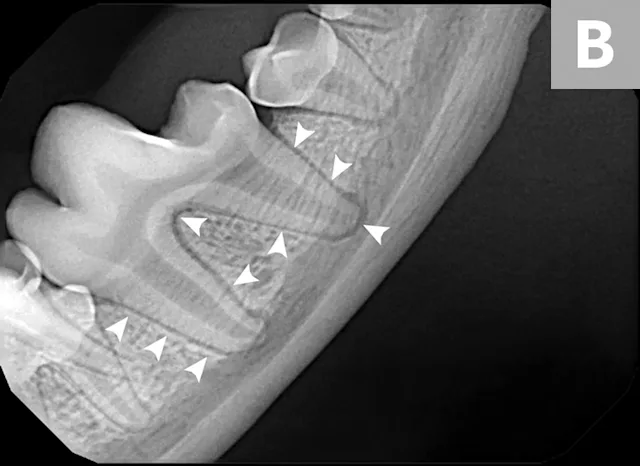

Dental x-ray of mandibular first molar with arrowheads pointing to normal periodontal ligament.

Dental radiography should be included in a complete oral examination, as only ≈40% of the tooth and periodontium can be evaluated without radiographs. Bone loss from periodontal disease, periapical or endodontic pathology, tooth vitality, impacted teeth or retained roots, and other conditions (eg, neoplasia, tooth resorption) can also be assessed.<sup1-3 sup>

Routine full-mouth dental radiography can take minimal time when the appropriate technique is used and can be key in developing treatment plans.